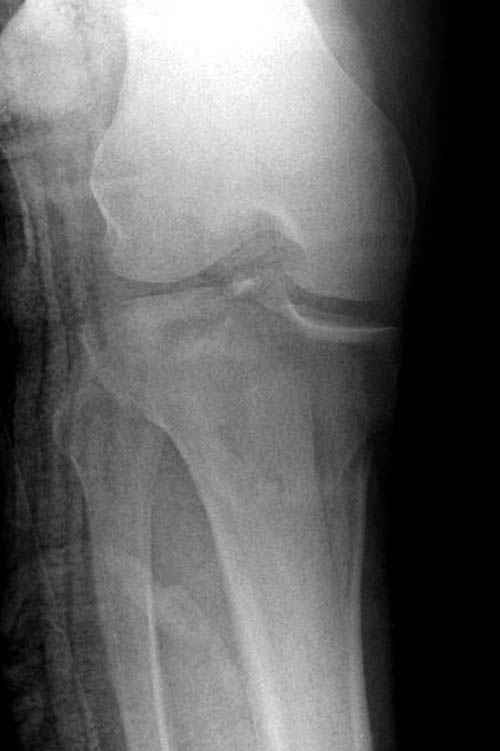

Трудно поверить, что разрекламированная Ортопедическая школа Восточной Украины позволяет такие странные снимки? На прямом снимке сохранен общий контур плато, но не известна судьба импрессии суставной поверхности. На полубоковой?, оставлен без репозиции задне-медиальный отдел, и навряд ли после такой фиксации можно удовлетвориться результатом.

Здесь как раз тот случай, когда результат зависит не только от мастерства хирурга, но и от наличия современных методов исследования. Например, КТ которая поможет рассчитать направления шурупов и установку импланта. Кроме этого, поможет определиться с доступом.

На представленных предоперационных срезах КТ огромный задне-медиальный фрагмент расположен больше кзади, чем медиально. Для планирования, кроме поперечных срезов, надо ориентироваться на корональные срезы, которые укажут топографию верхушки медиального фрагмента.

Представленные снимки не информативны, нужны отдельные качественные снимки коленного сустава и голени без ротации.